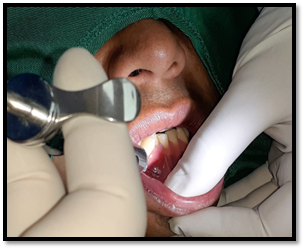

Imagen 5. Anestesia troncular al mandíbular y al mentoniano.

Anestesia: Se colocó la anestesia bucal localizada: 3 cartuchos 1.8 ml de lidocaína al 2% con epinefrina 1:80000 ppm. Se realizó técnica troncular: Nervio dentario inferior, nervio bucal, nervio lingual y al nervio mentoniano.